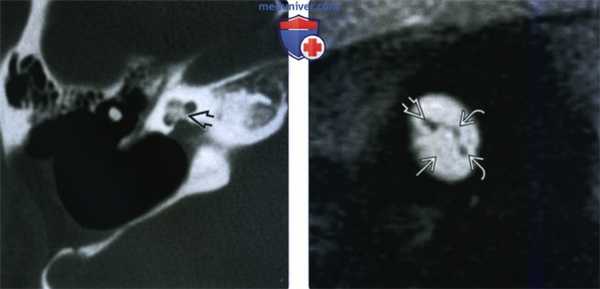

(Слева) При аксиальной КТ височной кости определяются типичные признаки запущенного сифилиса внутреннего уха. Визуализируются распространенные пермеативные изменения костей (кость, «изъеденные молью») внутреннего уха, среднего уха и сосцевидною отростка, и слуховых косточек.

(Справа) При корональной КТ височной кости у этого же пациента определяется пермеативная деминерализация слуховой капсулы с бляшкой (как при отосклерозе) на мысе улитки. Эти изменения обусловлены воспалительным резорбтивным остеитом.